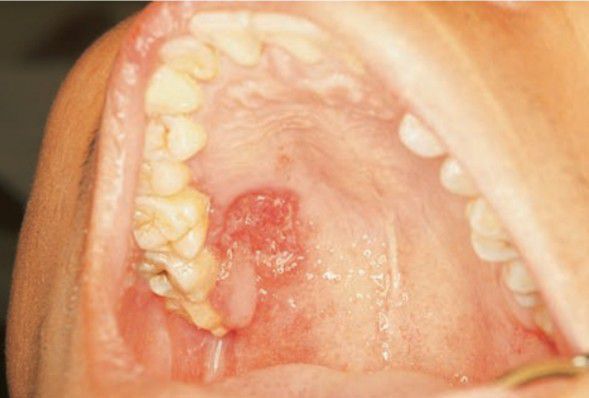

Tuberculosis of palate

Indurated, chronic ulcer that may be painful—on any mucosal surface